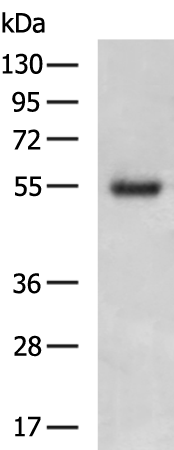

分类: 科研抗体货号: P11125别名: SP75, TPIS, HSD-3.8应用: WB,IHC反应种属: Human